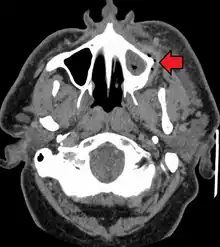

Dental caries can also cause bad breath and foul tastes.[17] In highly progressed cases, an infection can spread from the tooth to the surrounding soft tissues. Complications such as cavernous sinus thrombosis and Ludwig angina can be life-threatening.[18][19][20]